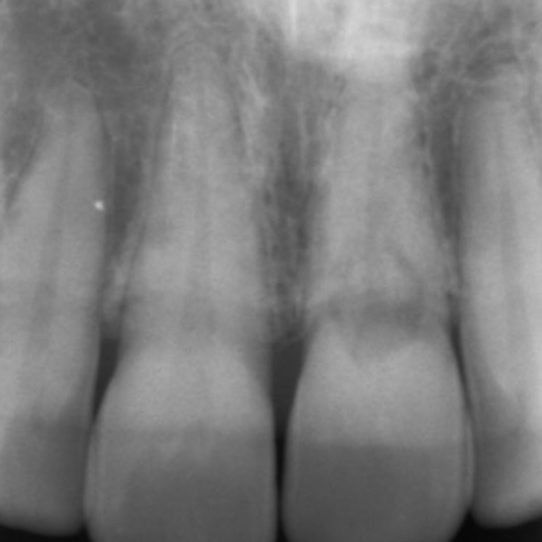

External cervical resorption typically presents as an asymmetrical radiolucency with irregular borders (Figure 4).

The outline of the root canal is visible through the lesion indicating the resorption is on the external aspect of the tooth.

The lesion may appear cloudier or mottled if it has progressed into a more reparative phase.